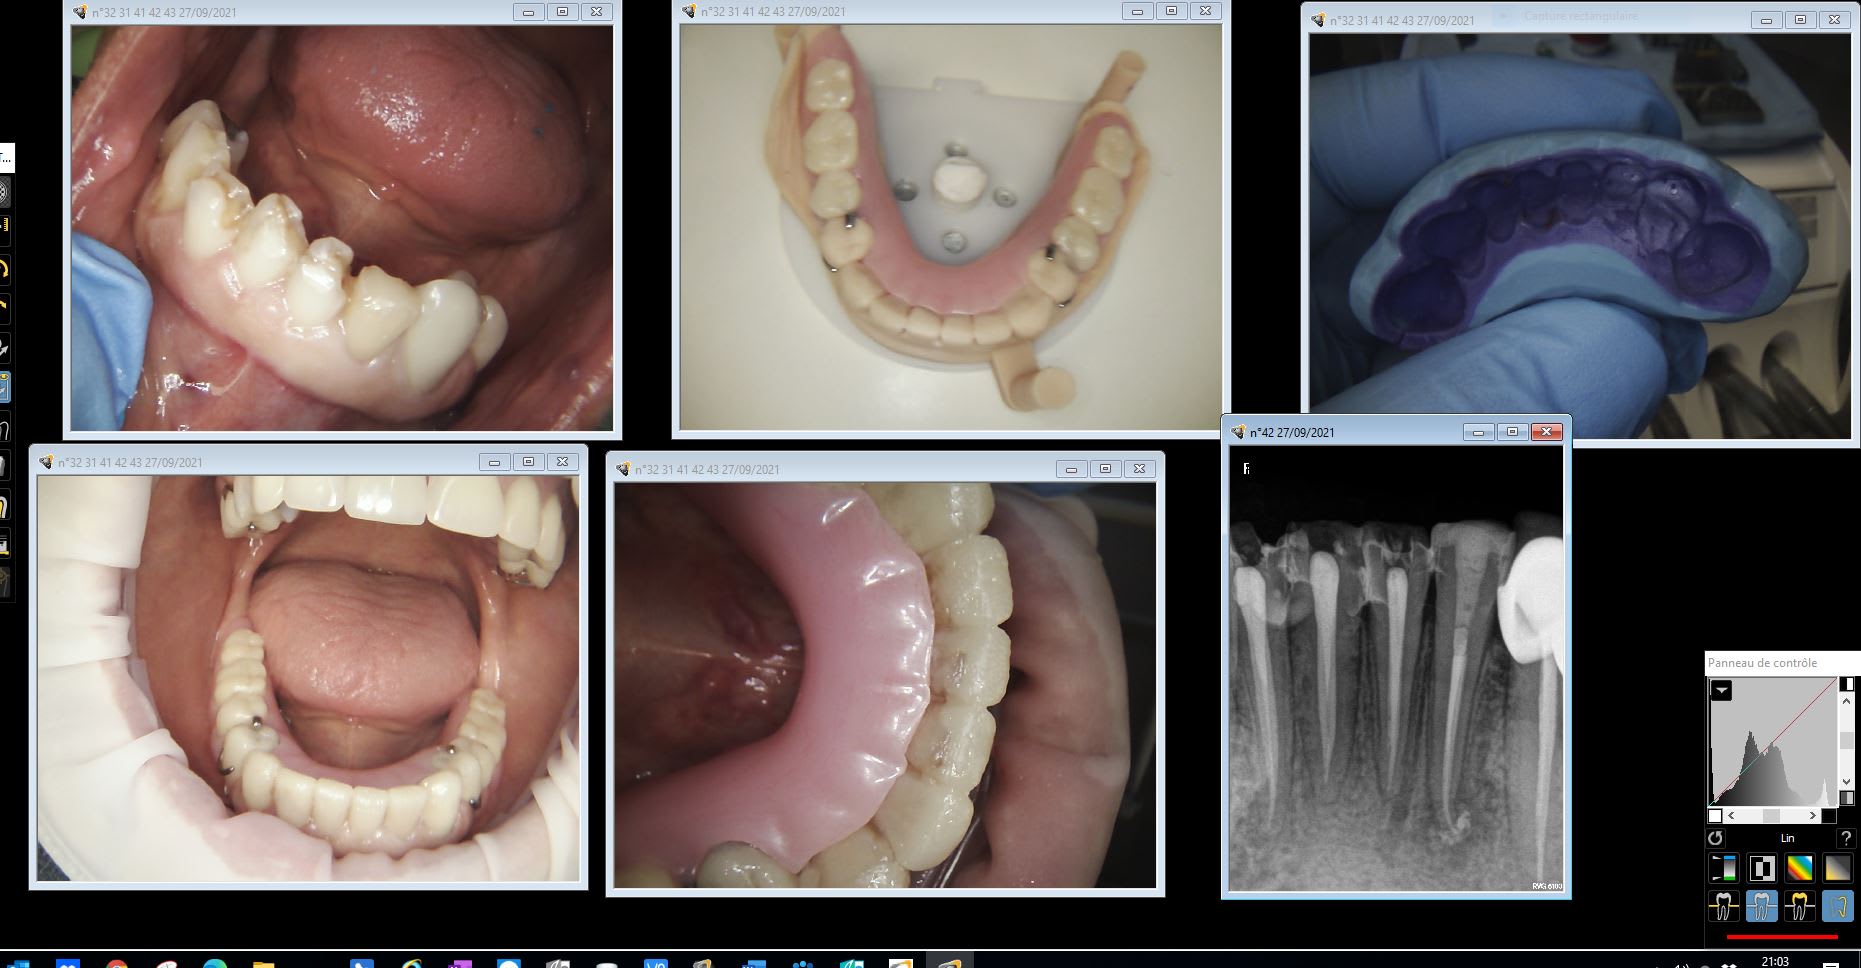

Par contre pour un cas global , comme il est il restera , ce n est pas l informatique qui va te modifier une reconstitution dans une nouvelle occlusion avec une baguette mabit .

Essayage moke up transitoire avant.

Moke up transitoire xtrudt - Eugenol

12/10/2021 à 21h16

Mais leur partiel prov avec leurs taquets façonnés... Parfait.

En définitif sur les incisives mandibulaires (encore de belles endo...) tu feras quoi chicot ? Des unitaires ? Des ic ??

2 par 2 sans ic.